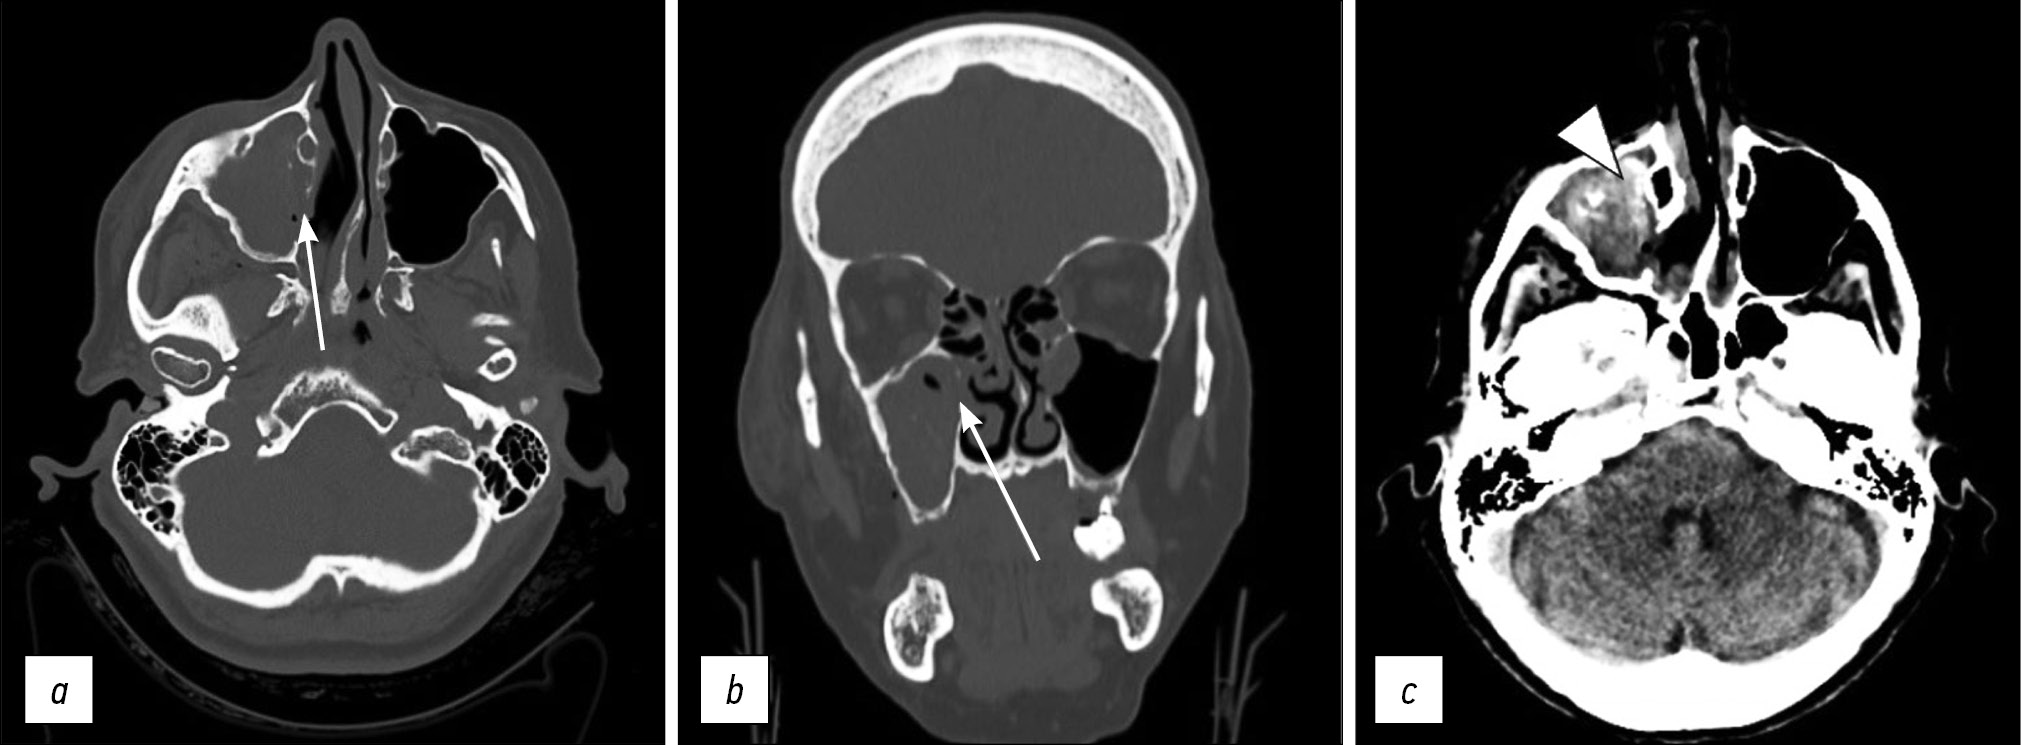

The patient was referred to the radiology department for noncontrast-enhanced high-resolution computed tomography (CT) on a 64-slice scanner, which showed unilateral right pterygoid plate fracture with signs of emphysema in the ipsilateral masticatory space (Fig. 1a, 1b). The CT investigation also documented the fracture of the medial wall of the right maxillary sinus with hemosine (Fig. 2a, 2b, 2c).

Fig 1: Axial (a) and coronal (b) CT scan with a bone window showing unilateral right pterygoid plate fracture (arrows) with air bubbles of emphysema (arrowheads) in the ipsilateral masticatory space.